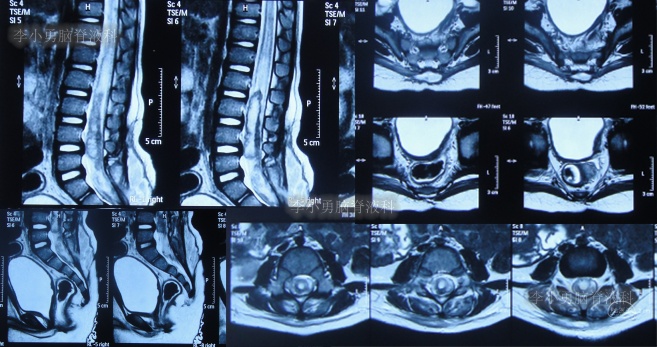

在第2家医院治疗13天即2022年5月24日,患儿仍间断高热,在医生建议下当天转至上级的第3家医院山东省某省级三甲医院,查脊髓核磁(图-2)后行腰椎穿刺有脓液吸出,给予腰大池置管术,但未见脑脊液流出,给予消炎、营养脑神经治疗。

图-2:2022年5月24日脊髓核磁